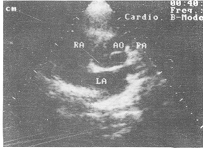

3. 主动脉瓣四叶畸形: 左室长轴观见主动脉瓣关闭呈“”形, 大血管短轴观呈“十”字形。 相邻半月瓣间见四处主动脉附着点, 开放时半月瓣向四个方向运动, 接近主动脉壁, 可清楚地显示大小不等的四个半月瓣, (图1,2)。

图1 左室长轴切面显示主动脉瓣四叶畸形呈“

”形

图2 大血管短轴切面显示主动脉瓣四叶畸形呈“+”形